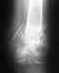

Действительно, есть значимое расхождение. Оно говорит о повреждении и неустраненном смещении в задних отделах таза. На снимке этот отдел срезан.

В диагностике помогут снимки с захватом их (прямой и inlet) и КТ. Вероятно, придется делать еще одну операцию.